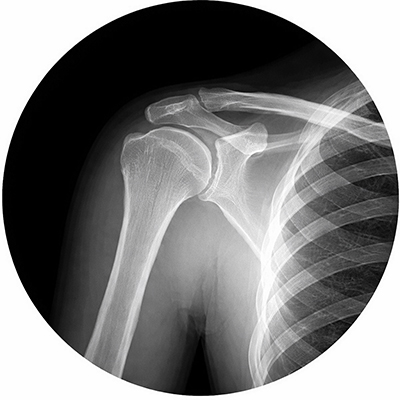

Рентген плечевого сустава

Особенности рентгена плечевого сустава обусловлены сложной анатомией и большой амплитудой движений в этой области. Из-за наложения теней грудной клетки, ключицы и лопатки важна правильная укладка пациента: для получения изолированного изображения сустава без наслоений часто используют ротацию плеча внутрь или кнаружи, а также отведение конечности. При травмах укладку выполняют с максимальной осторожностью, иногда в положении пациента сидя или лежа, чтобы минимизировать смещение отломков и избежать дополнительной травматизации.

Полученные рентгеновские снимки позволяют увидеть и изучить целостность костных структур, их форму, врожденные особенности строения и степень патологических изменений костной ткани. При проведении этого исследования лучевая нагрузка на организм человека минимальна. Противопоказанием к плановому исследованию является беременность; в остальных случаях рентген плечевого сустава может быть выполнен при наличии клинических показаний.